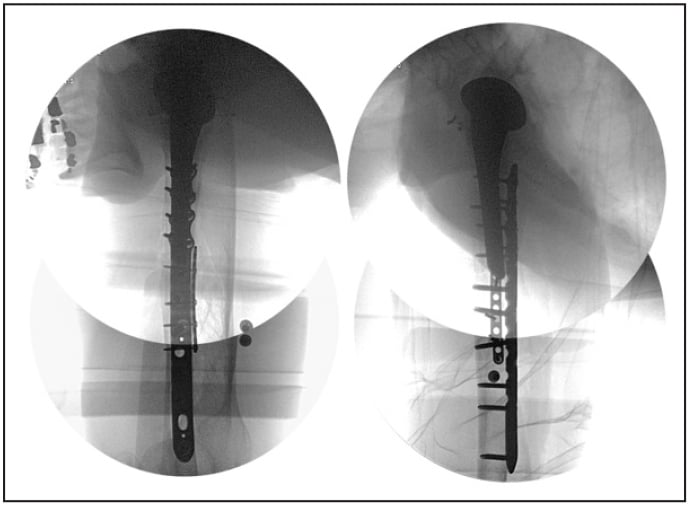

Intraoperatively, a posterior triceps splitting approach was used and the radial nerve was dissected and protected. The humeral stem was confirmed to be well fixed within the cement mantle. Next, the transverse fracture was reduced using clamps placed inside drill holes and the clamps replaced with a medial mini-fragment plate to hold the reduction. A periprosthetic plate used posteriorly allowed for placement of multiple bicortical and transcortical screws around the implant stem (Fig. 2). The plate was fixed distally in standard fashion with bicortical non-locking and locking screws.

Figure 2: Intraoperative fluoroscopy shows a dual-plate construct using mini- and large-fragment plates.